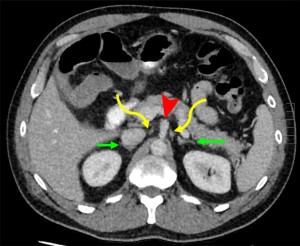

The celiac plexus is located in the retroperitoneum and consists of the right and left celiac ganglia along with the superior mesenteric ganglion. Each celiac ganglion lies on either side of the celiac trunk, medial to the adrenal glands, following their corresponding arterial vasculature. On CT, the ganglia exhibit a characteristic “discoid” or multilobulated appearance, best appreciated on axial images .

The tendency of pancreatic cancer to spread along nerves is likely attributable to the dense network of neural plexuses surrounding the pancreas. In pancreatic ductal adenocarcinoma, the most frequent sites of perineural spread are the celiac plexus and the plexus pancreaticus capitalis . Except for the celiac ganglia, the neural plexuses are not directly visualized at imaging, with the mesenteric arteries they follow serving as surrogate landmarks for detection, where PNS manifest as wispy increased attenuation or confluent perivascular soft tissue.